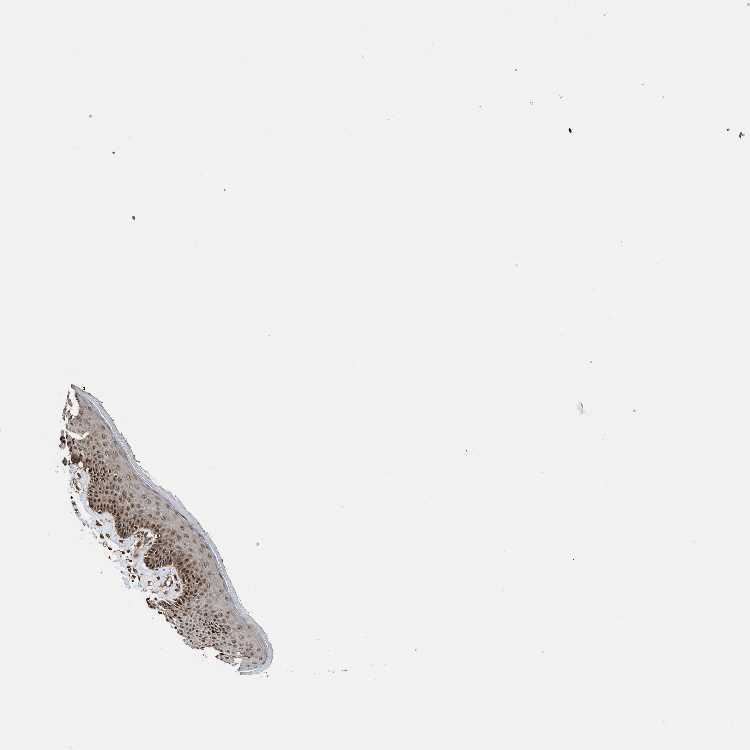

SKIN 1 - Antibody stainingi

Antibody staining in the annotated cell types in the current human tissue is reported as not detected, low, medium, or high, based on conventional immunohistochemistry profiling in selected tissues. This score is based on the combination of the staining intensity and fraction of stained cells.

Each image is clickable and will lead to virtual microscopy that enables deeper exploration of all samples and also displays staining intensity scores, fraction scores and subcellular localization as well as patient and tissue information for each sample.

Antibody HPA018481Antibody CAB017190

Langerhans Not detectedLow

Fibroblasts LowHigh

Keratinocytes LowMedium

Melanocytes LowMedium

SKIN 2 - Antibody stainingi

Epidermal cells MediumHigh